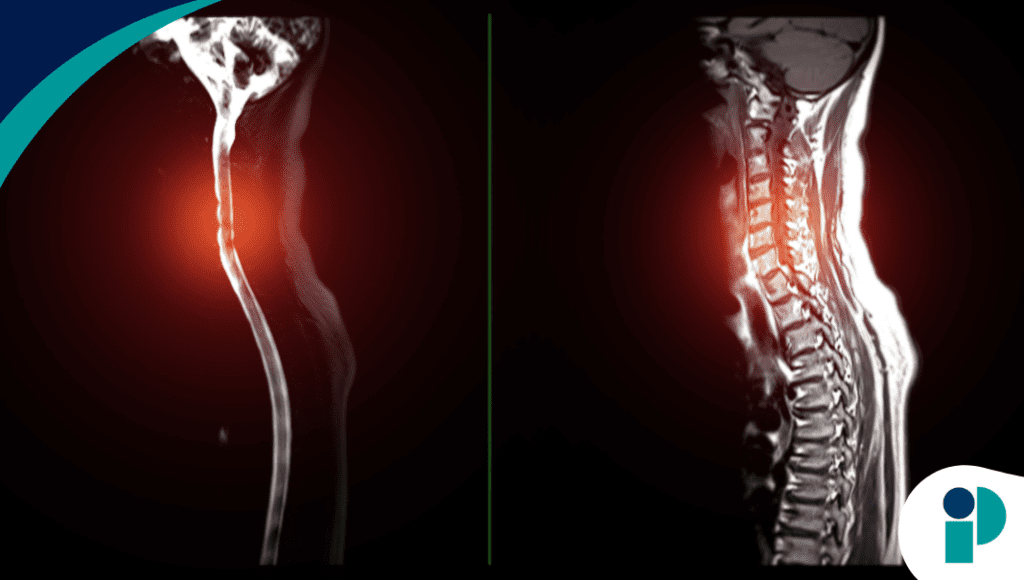

El ensayo incluye adultos entre 21 y 70 años con lesión de la médula espinal de al menos un año de evolución y presencia de dolor o espasticidad. La intervención consiste en sesiones de terapia manual tres veces por semana durante cuatro semanas, enfocadas en la localización de puntos dolorosos y su tratamiento mediante posicionamiento terapéutico suave. El estudio contempla 30 participantes en un protocolo clínico prospectivo de un solo grupo, orientado a evaluar cambios sintomáticos a corto plazo.

Entre las variables principales se analizan el dolor neuropático, la espasticidad muscular medida con la escala Modified Ashworth y la calidad de vida mediante instrumentos estandarizados de autopercepción de salud. Los investigadores registran cambios sintomáticos sesión a sesión, además de comparar resultados antes y después de la intervención para determinar la magnitud del efecto clínico observado.